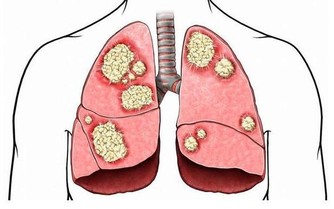

俗話說得好:「病來如山倒;病去如抽絲」...實際上,任何疾病的發生發展都有一個過程,在突發前都有一些身體上的先兆,只不過沒有引起我們足夠的重視罷了。隨著健康意識的增強,我們應該對人體發出的不良信號,給予足夠的重視,避免釀成大禍. 翻拍wikihow 一、起床後的四個信號 人的一天在不同階段身體的不良感受,就是在向您的健康發出警示信號。 1、清晨醒來如果頭暈、頭昏,可能是出現了頸椎骨質增生或血黏度過高等疾病; 2、如果在起床活動20分鐘後浮腫還不徹底消失,提示可能有腎病或心臟病; 3、晨起噁心嘔吐,除去懷孕的原因,如每天早上都如此,很可能是慢性胃炎或肝膽有病; 4、晨起小便,如果尿液棕色,提示肝臟可能出現問題。 二、清晨對鏡觀察臉色 洗臉時對著鏡子觀察,看看自己的臉色有沒有什麼異常: 1、如果發現自己臉色潮紅,可能與心臟病或高血壓有關; 2、如臉色帶黃,還伴以身體疲倦,很可能是黃疸型肝炎; 3、如發現眼睛顏色改變,充血、渾濁、色黃,應馬上去醫院看醫生; 4、如眼瞼蒼白,提示可能患了缺鐵性貧血; 5、如眼角膜出現一圈模糊的灰環,說明心臟可能有問題,如果是30—50歲的男性應馬上到醫院就診。 三、刷牙留意牙齒口氣 1、刷牙時如果牙齦出血,很可能是牙周病,因為如果牙齒健康是不會出血的。牙齒出血也可能與肝病有關。這種現象在慢性肝病患者中很普遍,還會伴有鼻子流血、月經過多。主要原因是肝細胞損傷後,肝臟產生凝血因子的功能下降,繼而凝血機制發生障礙。一般牙出血的肝炎病人可以服用維生素C、維生素K及其他止血藥來緩解病情。 2、如果出現口臭、口氣重,則可能是牙周病引起,同時,胃病、肝病、糖尿病等全身性疾病或缺乏微量元素鋅和維生素B都可能導致口臭。比如,胃幽門螺桿菌感染可引起持續性口臭,還常伴有不同程度的飢餓感和胃痛。一旦吃飽喝足,口臭會隨之減輕,而隨著幽門螺桿菌的根治,口臭也會自動消失。 3、口中有氨味要格外注意腎臟的健康。當腎功能衰竭時,由於不能正常代謝,體內肌酐、尿素氮含量增高,口中就有一股特殊的氨氣味。 四、飲食上的大病先兆 1、如果總感到口渴,要去查查血糖和糖耐量,看有沒有可能是糖尿病; 2、如果在清晨4—5點鐘醒來有強烈的心慌飢餓感,並且伴有疲乏無力,直到吃早餐後不舒適的感覺才逐漸消失,提示可能是糖尿病傾向; 3、如果吃油膩食物後上腹部疼痛,並放射到右肩背部,很可能是患有肝膽疾病; 4、如果食慾亢進,體重卻減輕,可能患了甲狀腺功能亢進症; 5、如果沒有食慾,見到油膩就噁心,易疲勞,可能是患了肝炎; 6、如果出現食不知味,並伴心悸、多夢、失眠等。這就意味著心臟功能受到了損害,是操勞過度所致。當口中乾澀,舌苔厚重,嘗不出食物的滋味時,尤其要警惕,防止心臟發生病變; 7、如果飯後總是出現反酸、腹脹或腹痛等症,提示積食了,要多吃新鮮蔬菜,三餐要注意清淡,以易於消化。 五、手部的警示信號 1、觀察自己的雙手,如果發現指尖比指節更粗大,可能是患有較嚴重的肺部疾病; 2、如果指甲生長緩慢,沒有光澤並且變黃變厚,提示淋巴系統出了毛病; 3、如果手背靜脈突出,並且隨著年齡增加越加明顯,也提示有心臟病的可能; 4、如果手掌泛紅,可能是肝臟出現問題及內分泌失調; 5、如果過度興奮或緊張時手掌常潮濕出汗,可能有甲狀腺的異常; 6、手發抖可能是甲亢,也可能是帕金森病。 六、眼睛的警示信號 1、眼睛發花,眼角乾澀,看不清東西。這是肝功能衰弱的先兆。如果按一按肝臟四周,就會有發脹的感覺,這時除了及時就醫外,還要注意用眼衛生,不要讓眼睛太疲勞; 2、如果經常眼睛疼痛,除了用眼疲勞外,老年人出現這種情況要提防青光眼。